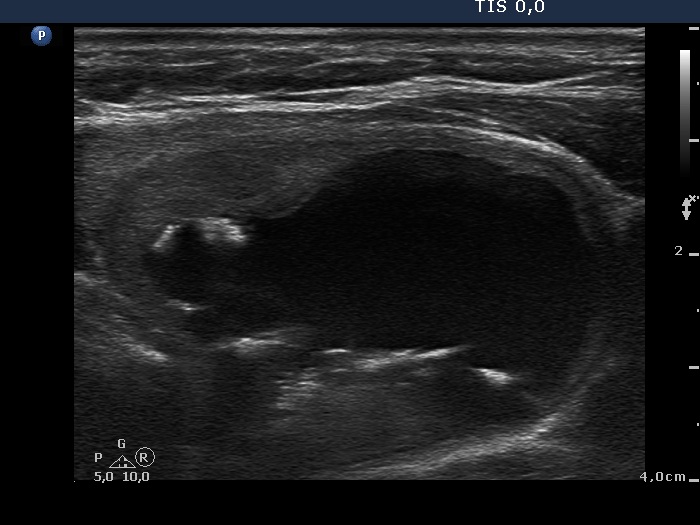

Benign Hashimoto's thyroiditis (cytological diagnosis) - case 1652

First, we demonstrate two cases of Hashimoto's thyroiditis with pronounced fibrotic changes. Both present pale and bright hyperechogenic granules and lines corresponding to normal and excessive connective tissue. Neither of the discrete areas are nodules in a pathological sense.